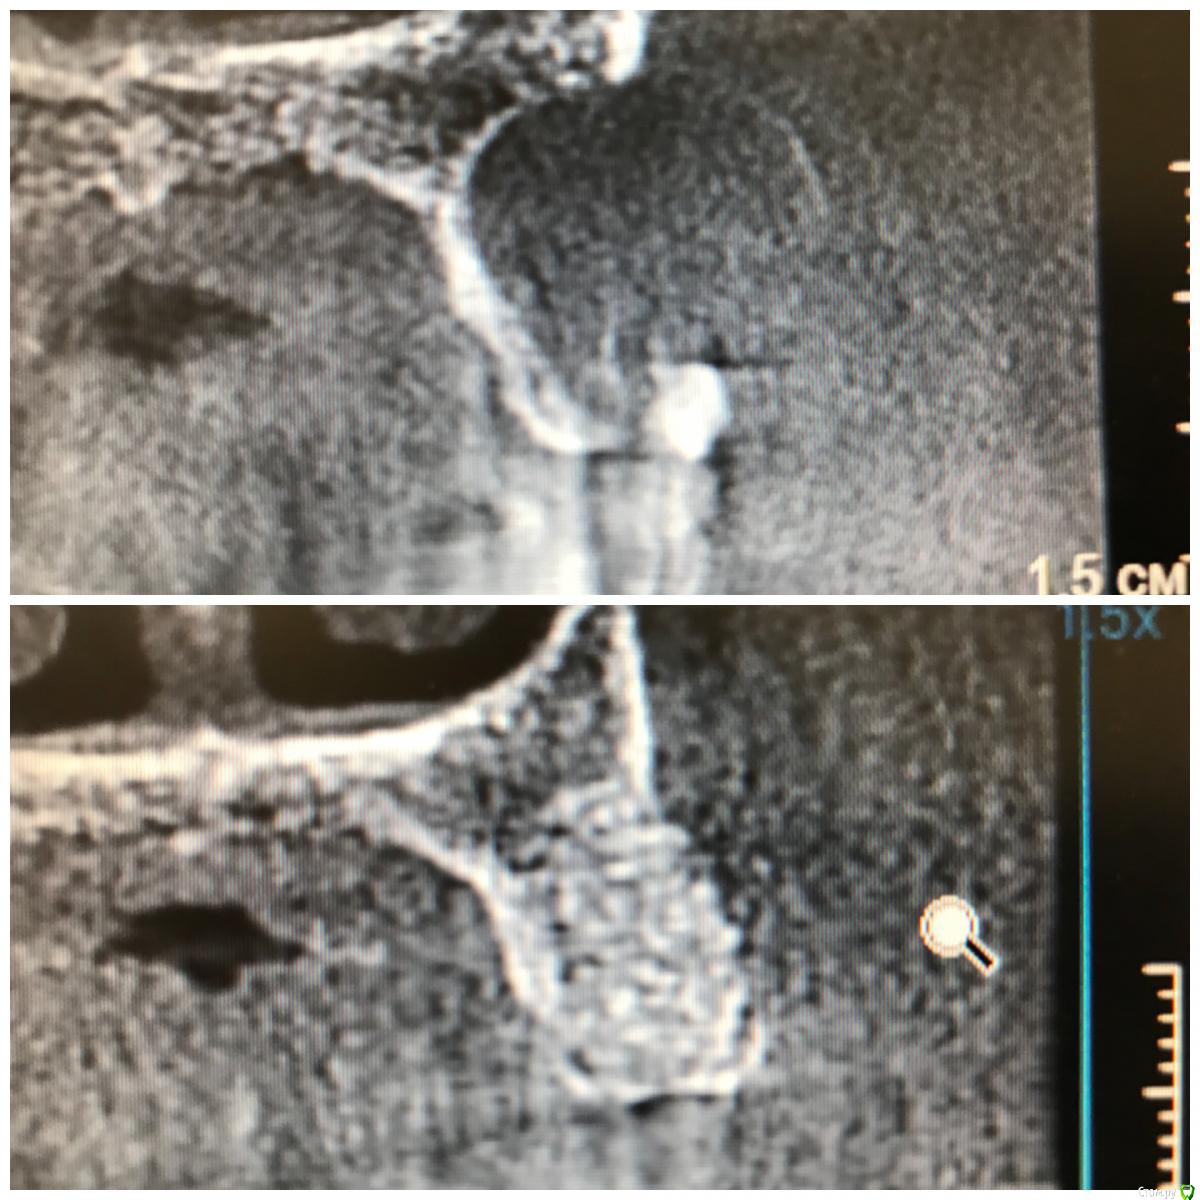

колесников Опубликовано 5 декабря, 2017 Поделиться Опубликовано 5 декабря, 2017 Пациентка N обратилась с жалобами на «выбухание дёсны» в обл 24. На клкт однотогенные кисты в/ч и значительные деформации гребня. От имплантации в перспективе категорически отказалась,потому было решено провести лишь подготовку гребня под чсп ( хотя было желание сделать открытый синус в обл 16/26 доступом через кистозную полость). Удаление причинных зубов без откидывания лоскута,вылущивание и кюретаж. Дефекты заполнены кортикальным аллографтом Sureoss,перекрыто бугром на ножке и vip ст. Был сдан чсп. Повторный визит через 7 мес. На клкт коегде кистозный свод просел. Видимо не достаточно графта было оставлено. Гребень выраженный,широкий. Случай показательный в плане эффективности и стабильности консервации лунки,очевидно что чсп не оказывает деформирующкно влияния на аугментированый гребень. По поводу удалить и подождать или удалить,заполнить и подождать,еще Carlos отмечал ,что кистозное выбухание в пазуху надо использовать для получения объема в зоне предстоящей имплантации. PS.Неудачи встречаются. Они связаны с нарушением герметизма лунки: некроз лоскута,распад сгустка и инфицирование графта. У меня было 2 жестокие неудачи,в первом случае пациент активный курильщик,второй любитель коньяка. В обоих случаях дополнительно применялся A-PRF ,но даже он не смог противостоять такому деструктивному влиянию агрессивных сред. 3 Ссылка на комментарий